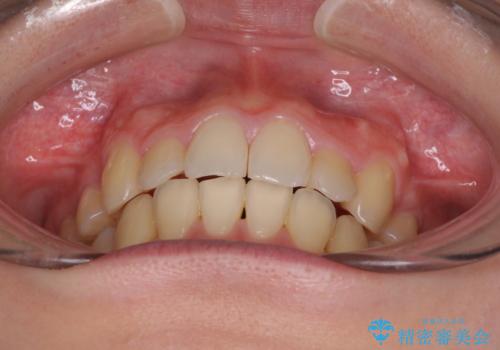

- 上下の八重歯や乱杭歯を気にして来院され患者様です。

スペースを確保するため、上下左右の第一小臼歯を抜歯し、ワイヤー装置に矯正することとしました。

その後スペースを閉じるために時間を要しましたが、満足のいく仕上がりとなりました。